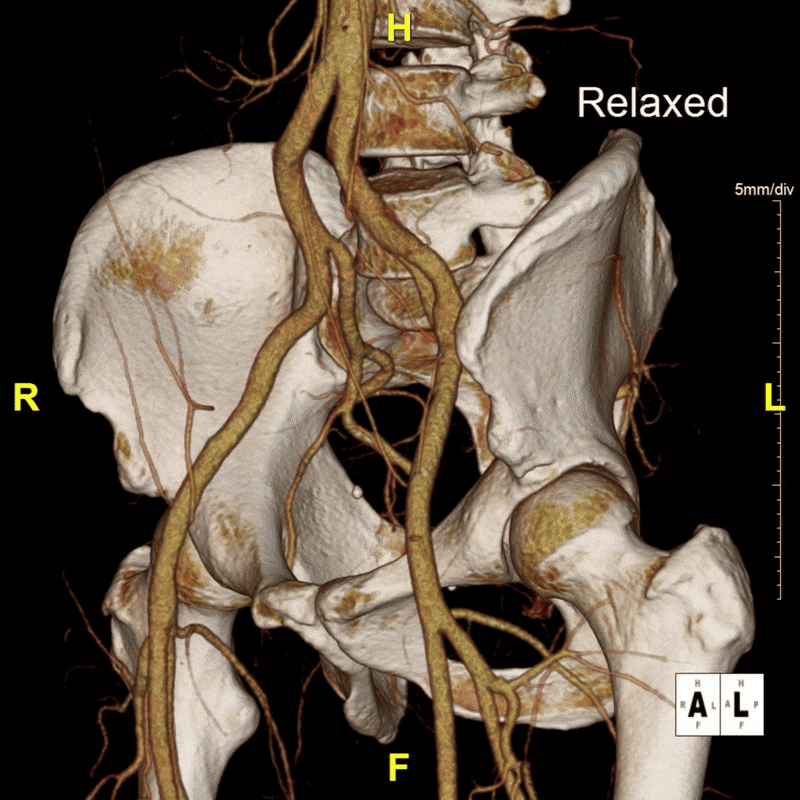

To better visualize the iliac anatomy, CPR loops were created to trace the artery along its course in both relaxed and stressed positions, allowing direct comparison of lumen size and curvature. VR views were generated with and without pelvic and femoral bone to show surrounding anatomical relationships. These complementary views help clarify how limb motion influences vessel shape and highlight narrowing that may be subtle or difficult to appreciate on axial slices alone. (Learn more about CPRs here, and VRs here).

Figure I: Targeted volume renders of both the relaxed and stressed positions.

When the patient moved into the stressed position, the right external iliac artery showed two areas of luminal narrowing (a temporary decrease in the size of the vessel’s opening). One narrowing was more proximal (closer to the vessel’s origin near the pelvis) at about ten to twenty percent, and the second was more distal (farther along the vessel toward the leg) at about thirty to forty percent. Both returned to a widely patent appearance (fully open) when the leg moved back to a relaxed position.

The left external iliac artery remained patent across positions, and the common iliac arteries were tortuous (naturally curving) without any fixed stenosis. This pattern aligns with external iliac endofibrosis, where motion causes the artery to change shape rather than a fixed obstruction, highlighting why positional imaging can reveal abnormalities that may not appear on routine resting studies.